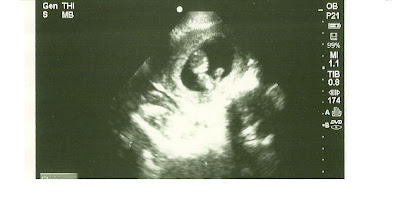

Hours later, the doctor, frazzled and grey, pressed the ultrasound scanner to my barely there baby bump and looked at the monitor screen. "He looks like he's praying." (Later, I tell Ryan, "If he/she lives, and it's a boy, we need to name him Daniel, after the man of prayer.")

Another doctor's appointment, another strong heartbeat. This time, I see a tiny perfectly formed skeleton and wee fingers and a tiny adorable nose. (Good heavens. I grew bones. I've never done this before, you know.) It is a shockingly generous gift to grow life. Who am I that I should grow a human soul?